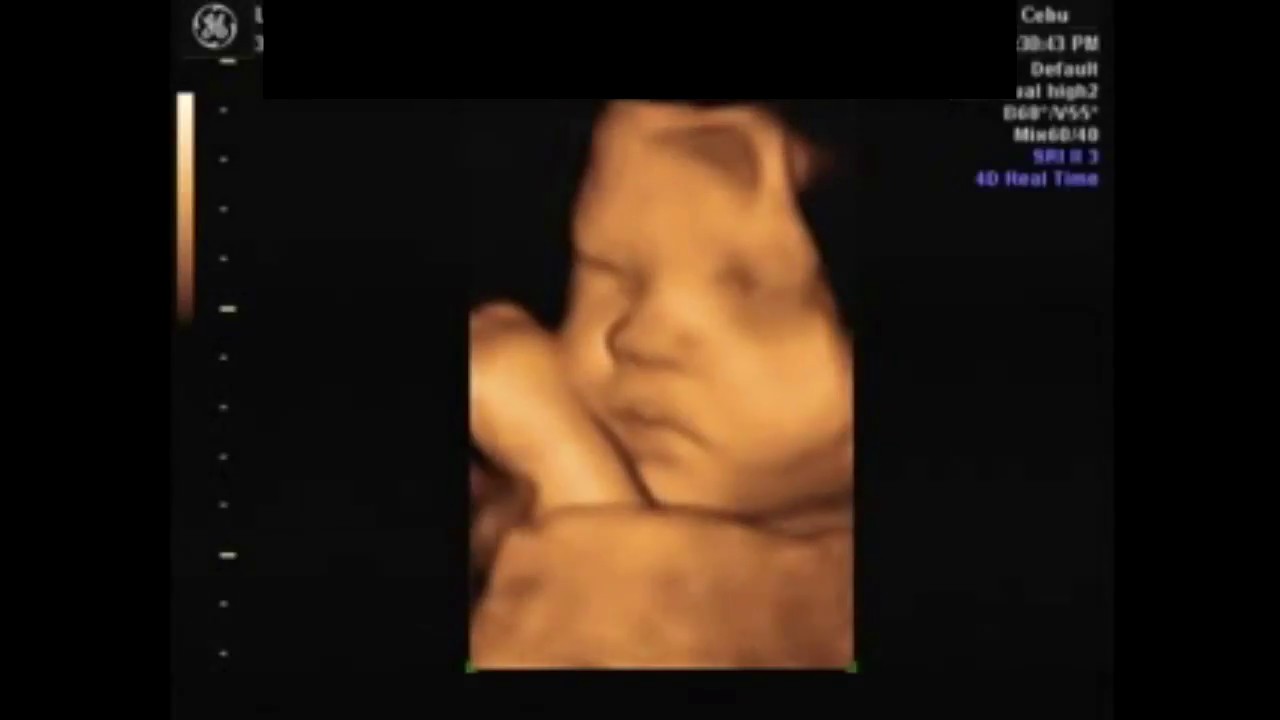

Cuanto cuesta un ultrasonido 3d. El ultrasonido o ecografía es un método de diagnóstico por imagen en el que se utilizan sonidos de alta frecuencia emitidas por una sonda llamada transductor y que se dirigen hacia el órgano o tejido que se desea estudiar el rebote de estas ondas sonoras en la superficie de la estructura se recoge y codifica en una computadora para mostrase en la pantalla del equipo de ultrasonido. Para los pacientes cubiertos por el seguro de salud los costos de tu bolsillo generalmente consisten en un copago de 10 50 o más o coseguro de 10-50 o más. El ultrasonido 3D sirve como punto de partida para la tecnología de última generación conocida con el nombre de ultrasonido 4D la cual se encarga de recopilar las imágenes obtenidas mediante la prueba de ultrasonido 3D y de acoplarlas en una cinta de video grabada en tiempo real permitiéndole de esta manera a los doctores e investigadores poder estudiar el.

Todas nuestras sesiones incluyen un examen médico diagnóstico completo y un informe que podrás llevar a tu médico para evaluar el bienestar de tu bebé. Costo de ultrasonido 3D en Similares Catálogo de fabricantes de Ultrasonido 3d Software de alta cuanto cuesta un ultrasonido de embarazo. El Ultrasonido 3D tercera dimensión es una técnica de ultrasonido esta se usa frecuentemente durante el embarazo proporcionándonos imágenes tridimensionales de feto.

Cuanto Cuesta El Ultrasonido 3d O 4d Embarazadas Primerizas Babycenter